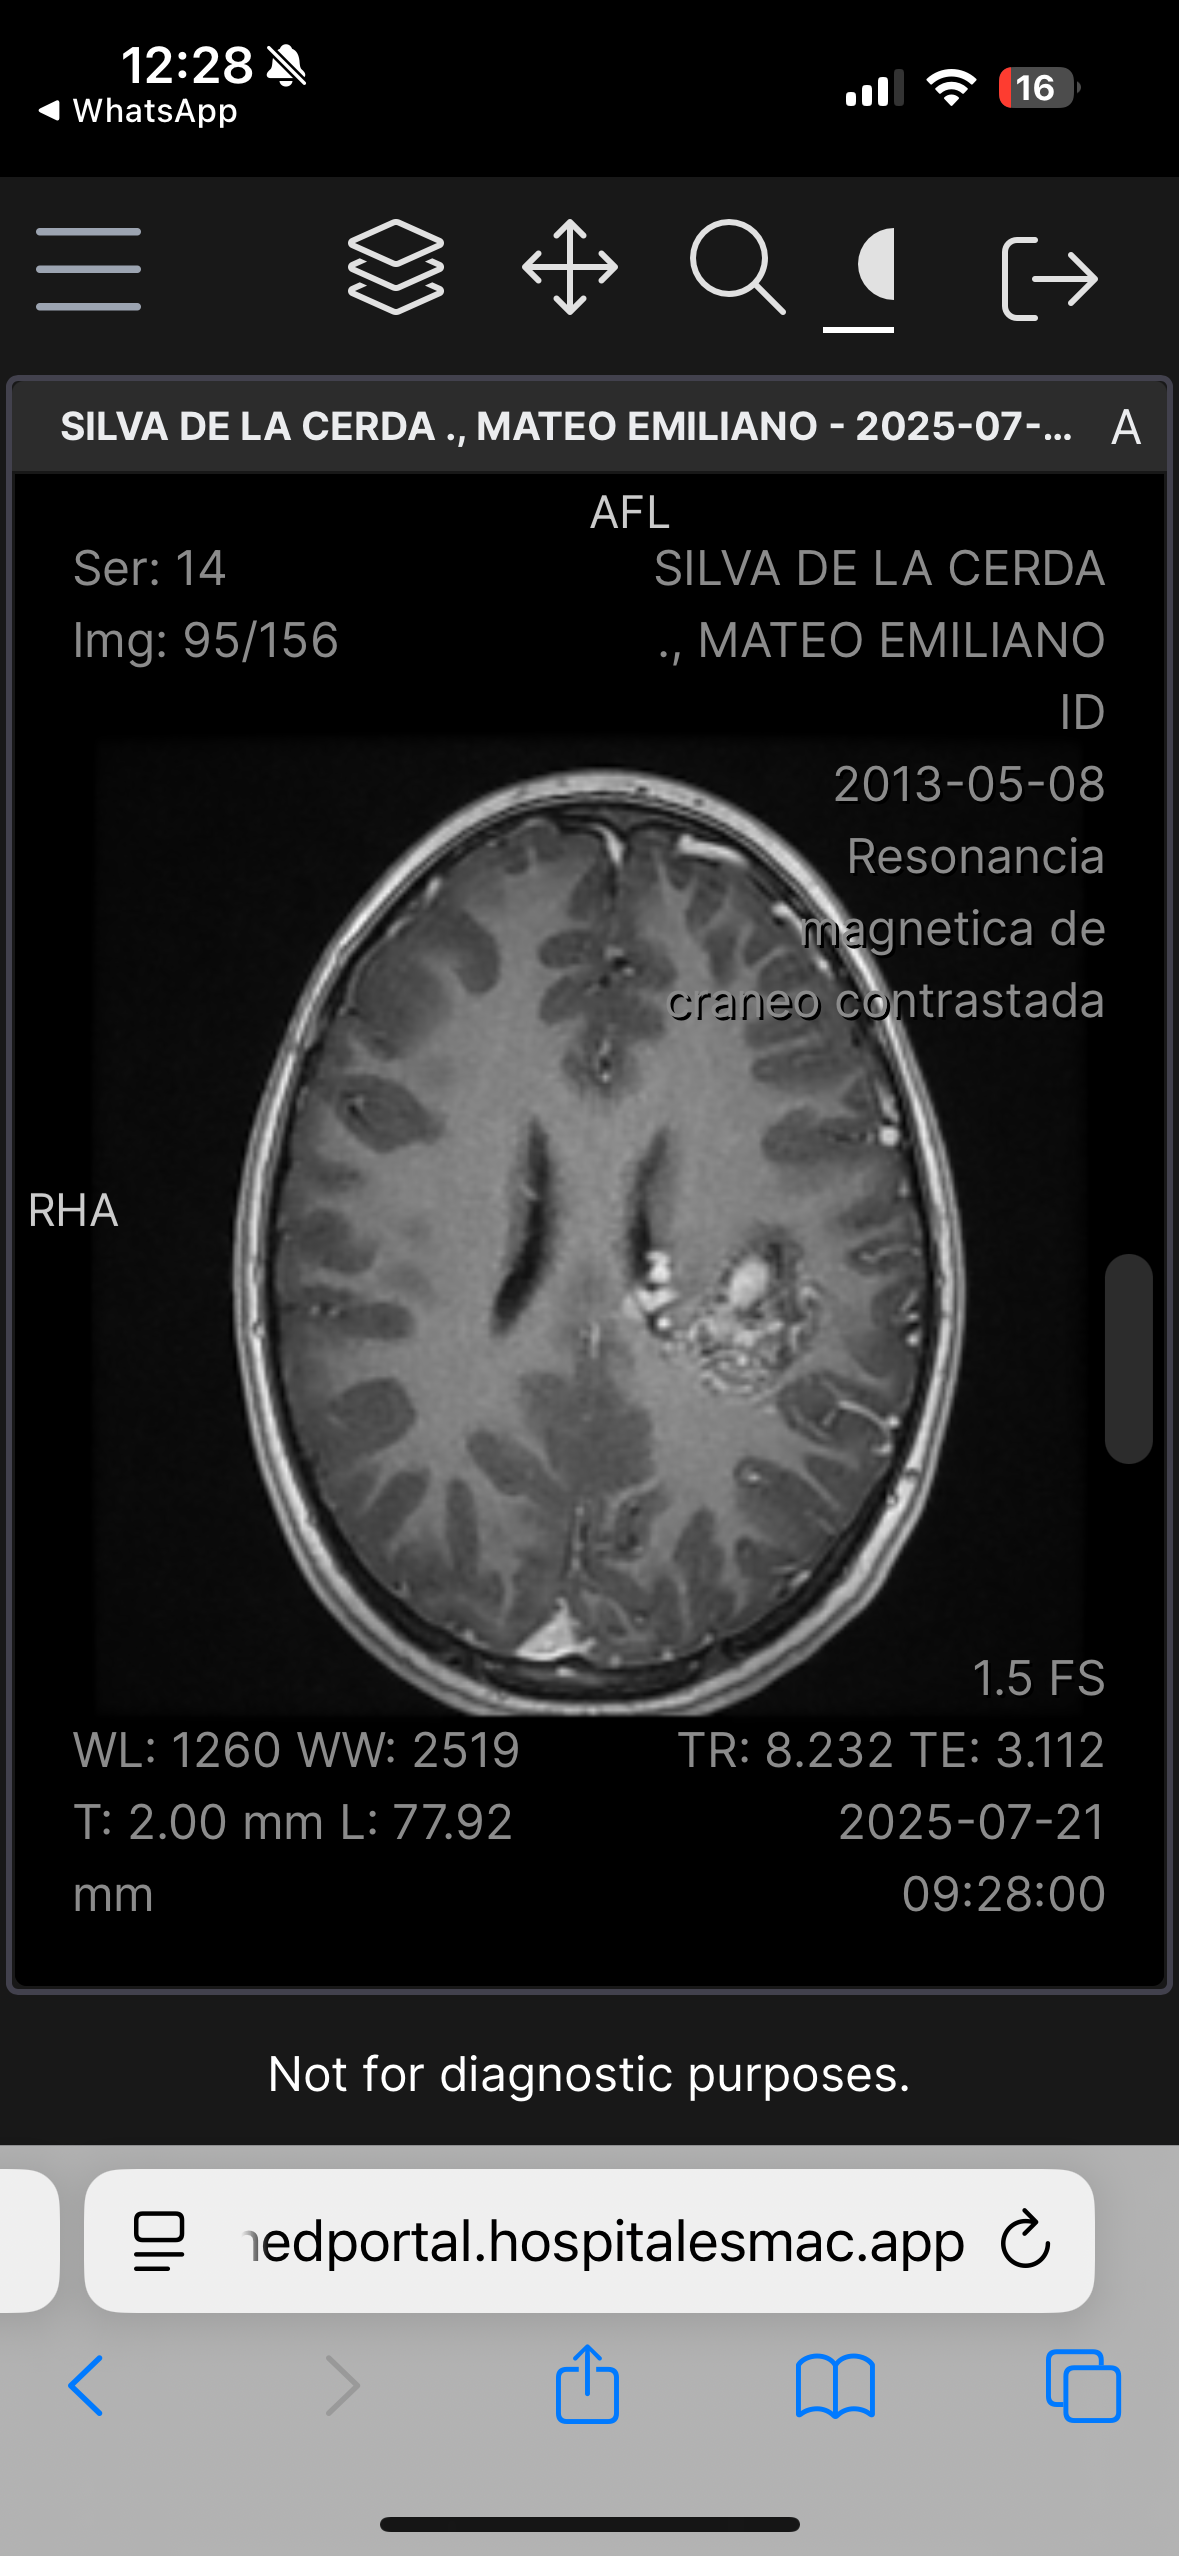

Hola, me llamo Mateo Silva De La Cerda, tengo 12 años, recientemente tuve un diagnóstico que cambió mi vida y la de mis papás, padezco una Malformación Arteriovenosa grado IV en la parte izquierda de mi cerebro, la cual hace un Nidus vascular. La complejidad de la malformación es por el aumento en la irrigación sanguínea los cual crea un tipo de “ nido” de venas y arterias, así como la profundidad en la cual se encuentra situada la malformación arteriovenosa en mi cerebro. Requiero una cirugía muy compleja, y la probabilidad de ocupar terapia intensiva posterior es muy alta.